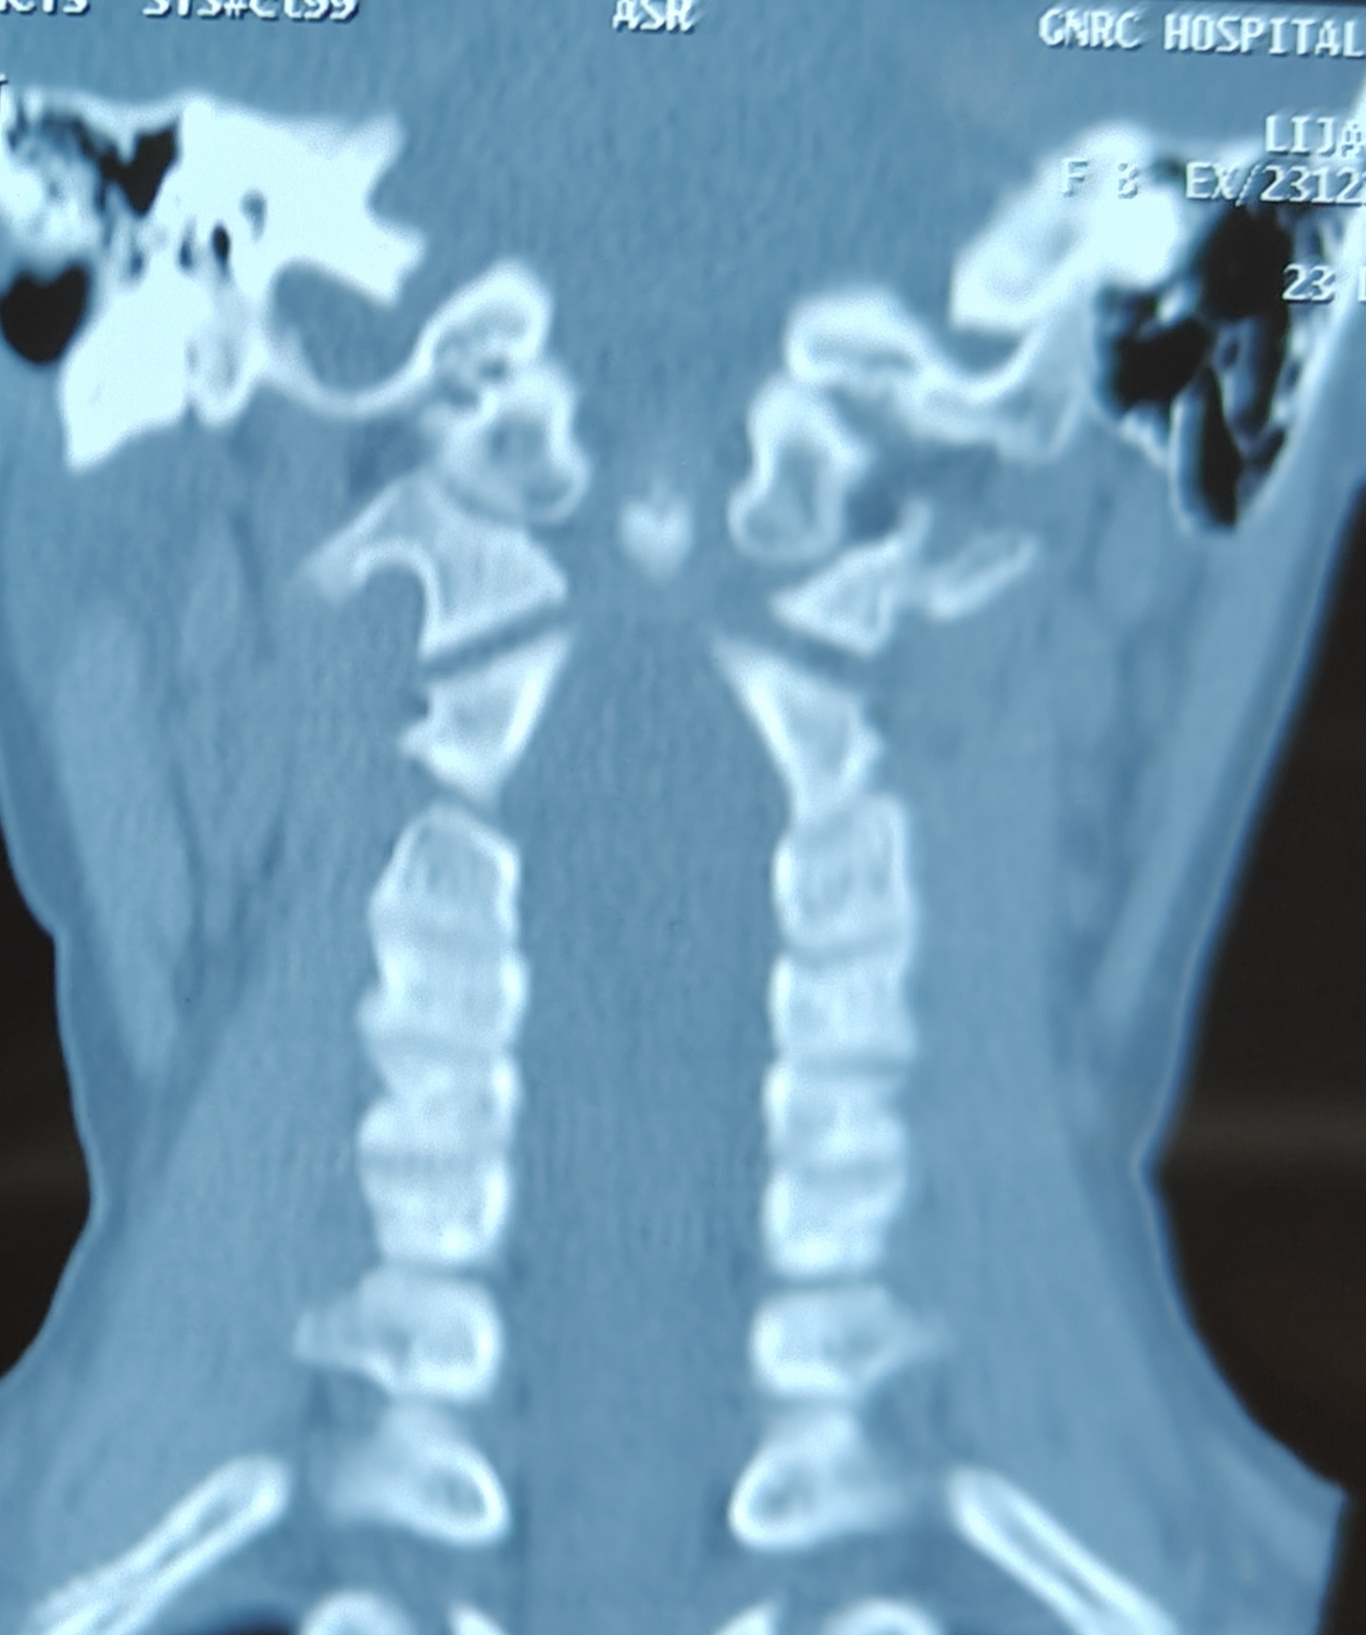

An 8 yr old child presents with squint and headache . CT , MRI shows Chiari 1 malformation with cord signal change

• Is there any instability ?

• Is there any impacted tonsil?

• What will be better..only bony decompression, duroplasty, tonsillar resection?